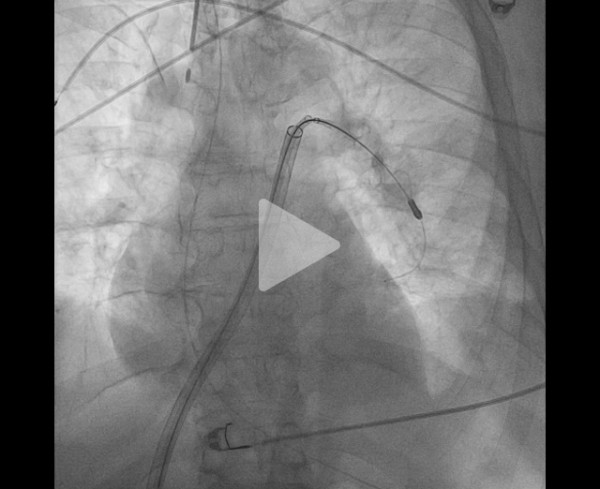

La procédure peut être complétée de l’utilisation de disques intra-artériels pour fragmenter le thrombus et faciliter son aspiration (Figure 9, Vidéos 5, 6 et 7).

Vidéo 5 : angiographie sélective

Vidéo 6 : disques mis en place en aval du thrombus

Vidéo 7 : retrait des disques